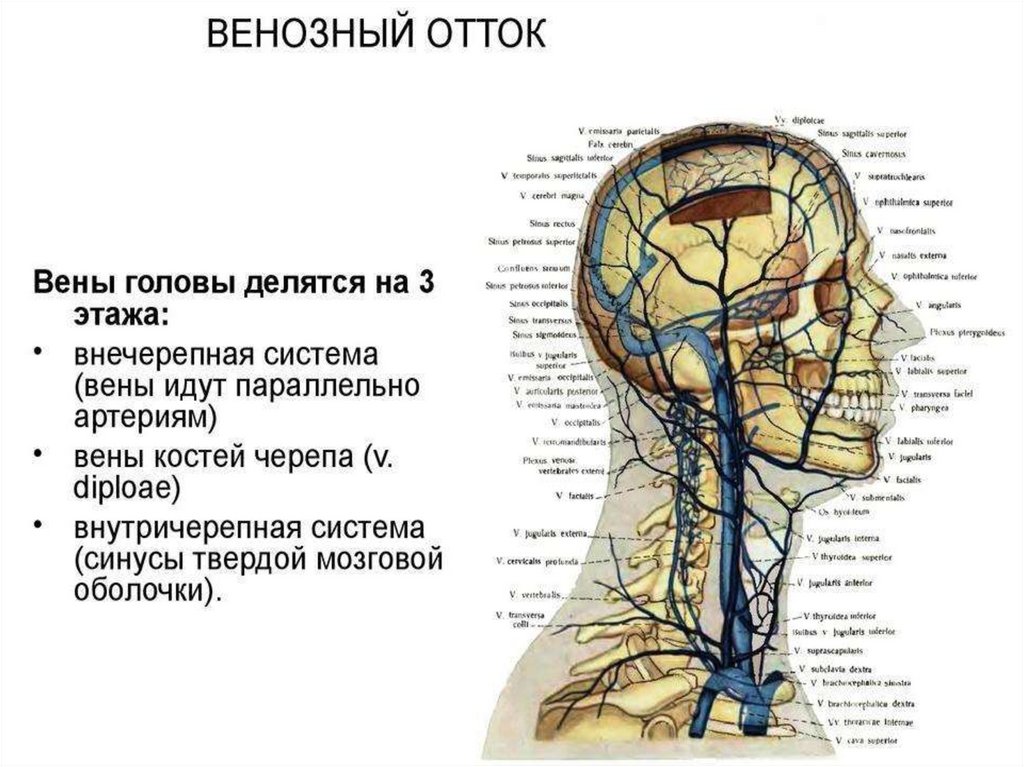

Анатомия внутренней яремной вены: КТ изображения